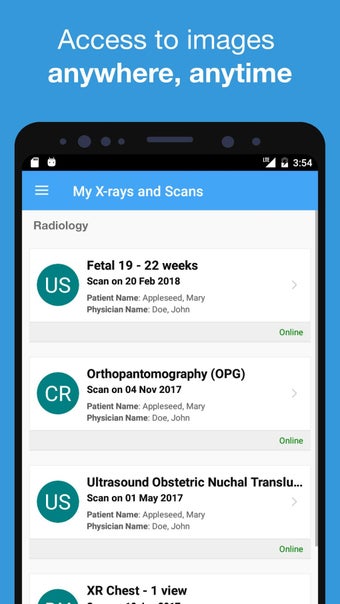

O aplicativo myPRP é usado por pacientes para acessar com segurança imagens e relatórios de exames realizados em uma clínica PRP Diagnostic Imaging.

Este aplicativo é destinado a pacientes do PRP Diagnostic Imaging prática. O aplicativo myPRP permite que os pacientes visualizem seus exames, leiam os relatórios e marquem consultas.

O serviço é seguro, rápido e fácil de usar. Você não precisará esperar muito para que seus resultados estejam prontos para visualização. Você receberá uma mensagem SMS quando seus resultados estiverem prontos para visualização.

Para acessar seus exames, você precisará de uma conta myPRP e uma senha. A conta myPRP é gratuita para criar.